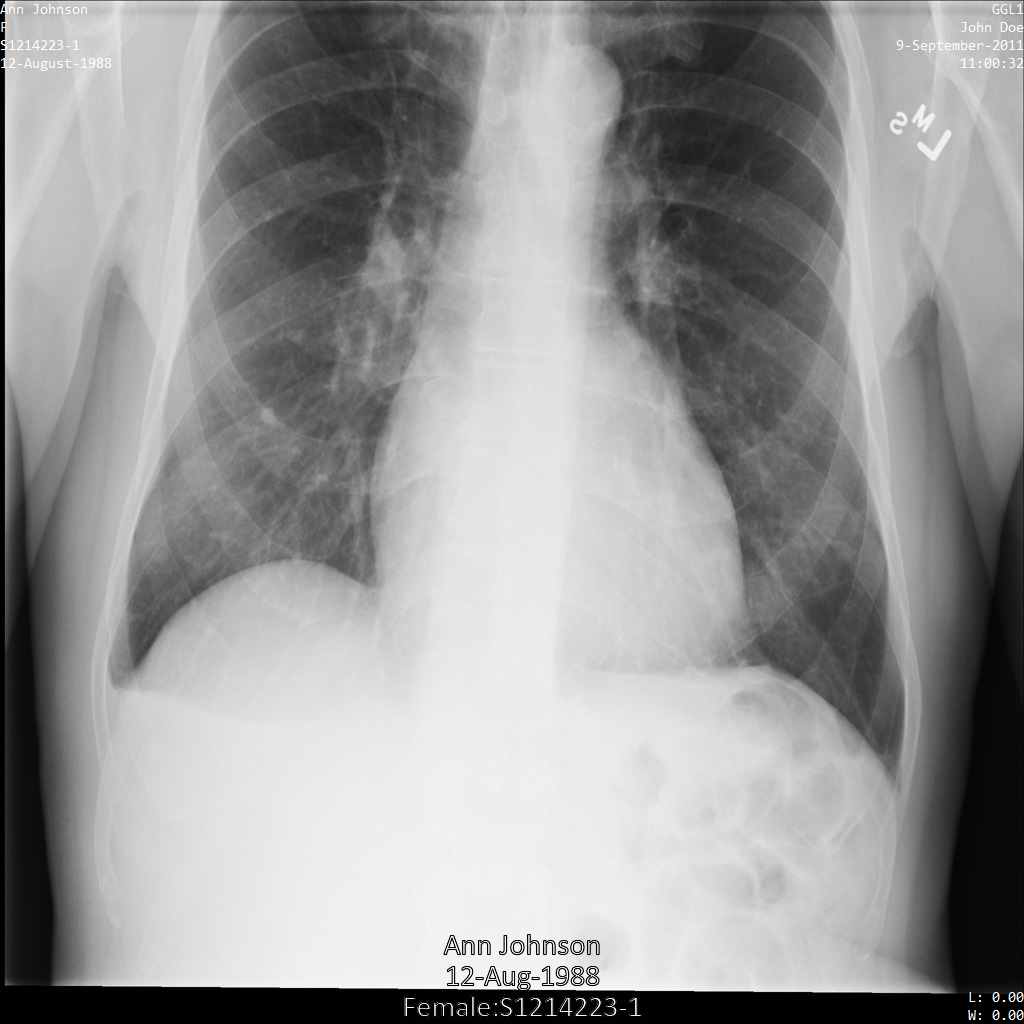

Descripción general de muestras

En las muestras de esta guía, se usa una sola instancia de DICOM, pero también puedes desidentificar varias instancias.

En cada una de las siguientes secciones, se proporcionan ejemplos de cómo desidentificar datos de DICOM mediante varios métodos. Se proporciona un resultado de la imagen desidentificada en cada muestra. En cada muestra, se usa la siguiente imagen original como su entrada:

Puedes comparar la imagen de salida de cada operación de desidentificación con esta imagen original para ver los efectos de la operación.